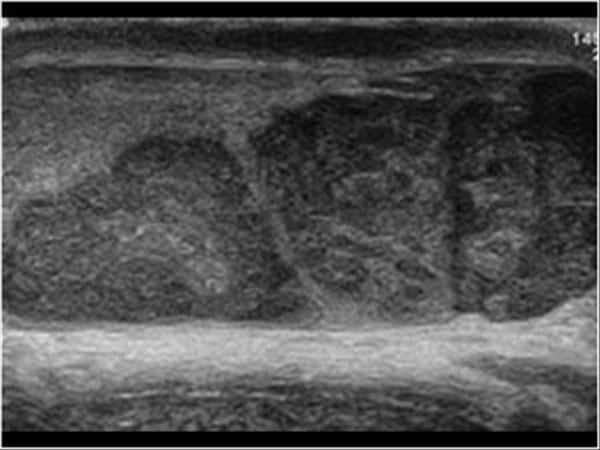

U tinh hoàn

# U tinh bào (Seminoma).